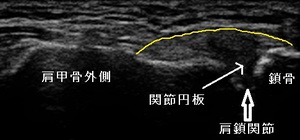

右肩鎖関節 超音波長軸像 左同部正常(健)側

診察後に超音波観察を実施した所、左健側と比べて右肩鎖関節内が腫れて肩鎖靭帯(黄色線)を押し上げて

ドーム状になっている様子が認められました。(左右上画像)

肩鎖関節は、肩甲骨外側の肩峰と鎖骨をつなぐ関節で、関節内には線維性軟骨の関節円板があり、関節の動きを

助けたり、関節の負担を和らげるクッションの役目をしています。

肩鎖関節炎は、繰り返しの関節への負担、ベンチプレスの様な高負荷なトレーニング、激しいスポーツ、転倒した際に

手を突いたりすると関節円板や関節を接続する肩鎖靭帯に傷が出来て炎症を起こしてしまいます。